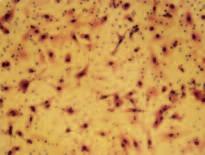

Immagine al microscopio di cellule leucemiche. Le sfere rosse del pacmen rappresentano gli enzimi collagenasi.

La foto nella pagina a fianco mostra una sezione trasversale al microscopio del fegato di un paziente con ‘leucemia linfatica’. Ciascuno dei piccoli puntini viola nella foto è un globulo bianco (in questo caso linfocita) che ha invaso il tessuto del fegato (aree rosa).

Considerando l’enorme quantità di questi puntini viola e il numero di enzimi che assimilano il collagene che ciascuno produce, è facile prevedere l’ingente distruzione del tessuto connettivo e il danno apportato all’organo da questo tipo di cancro.

Immagine al microscopio della leucemia linfatica

Globuli bianchi affetti di cancro (linfociti) invadono il fegato L’enorme quantità di collagenasi prodotte da queste cellule distruggono l’organo e causano insufficienza epatica.